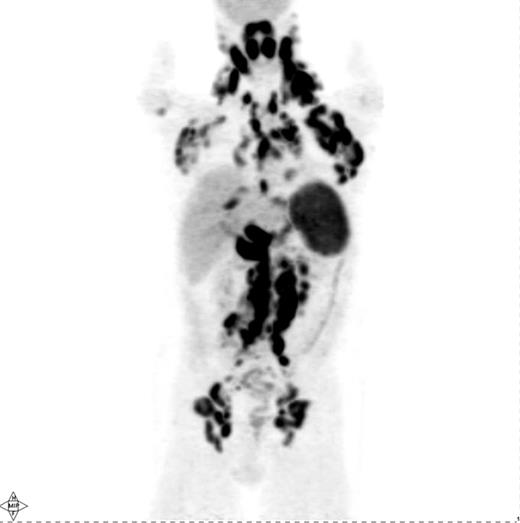

Several investigations have shown that PET is quite sensitive in detecting nodal and extranodal manifestations of HL prior to treatment (Figure 1 ).4–14 Most of these studies have reported on mixtures of HL and NHL patients, although a few have specifically addressed the utility of PET for staging of HL.6–13 In aggregate, these studies demonstrate that PET is able to detect an additional number of presumed HL sites compared with conventional staging methods, in particular CT and bone marrow biopsy (BMB). This results in a modification of disease stage (usually upstaging) in about 15–20% of patients with an impact on management in about 5–15%.4–12 However, one drawback of these studies is that they did not provide histopathological verification of all or, at least most, of the additional PET findings not shown by conventional staging methods. Reports of up- or downstaging patients by PET were mostly based on theoretical considerations that assumed that the additional PET findings truly represented lymphoma.8,9,10–14 Some studies used the disappearance of abnormal PET up-take following treatment as “proof” of the lymphomatous nature of these additional PET findings, a somewhat problematic approach considering that PET-positive benign entities such as fractures or inflammation may resolve with time irrespective of therapy.8,9,10–14 Nevertheless, several conclusions can still be drawn, particularly based on the studies in which reported modifications of disease stage or management were based on PET findings verified by biopsy, additional imaging (e.g., MRI) or by posttreatment morphologic regression (by CT) of PET-positive lymph nodes presumed to be normal on pretherapy CT.4–7,10 First, PET is able to detect focal or multifocal bone/bone marrow involvement in HL patients with negative iliac crest BMB, which could frequently be verified by guided biopsy of the PET-positive sites or by MRI.5–7,12,15–17 On the other hand, diffusely increased bone marrow uptake on PET may be due to reactive myeloid hyperplasia characteristic of some HL patients rather than lymphoma.16 In general, even focal/multifocal PET findings in the bone/marrow in the face of negative BMB should be confirmed whenever a change in treatment is contemplated based on PET. Second, PET alone is unreliable in detecting bone marrow involvement, particularly of limited degree (i.e., ≤10–20% of marrow space); an estimate of PET sensitivity for detecting marrow infiltration in HL based on a recently reported meta-analysis was 76% (95% CI 47–92).17,18 PET cannot, therefore, replace BMB in the staging of HL, at least based on currently available data. Third, PET and CT lead to concordant clinical stage in the vast majority of HL patients (60–80%).7–13 However, several reports suggest that discordant findings occur in both directions: PET demonstrates abnormalities undetectable by CT resulting, on average, in altering stage in 15–20% of patients and CT shows abnormalities undetectable by PET with an impact of a similar magnitude (i.e., 10–20%) on stage assignment.7–13 Abnormal findings seen only by PET with the potential for modifying disease stage or management include lymphomatous involvement of normal-sized lymph nodes by CT criteria (i.e., ≤ 1 cm in short axis), splenic and hepatic infiltration.4–14 Although most studies show that PET-negative/CT-positive findings are less common than the reverse, it is clear from a number of investigations that PET alone cannot replace CT for pretreatment staging of HL.7,8,10,12 Rather, the modalities are complementary. Fourth, based on the complementary information from PET and CT, it appears likely that a PET/CT scan, which combines a PET and a CT scan in a single study, performed in the staging setting using i.v. contrast, will provide at least equal information to that provided by PET and a separately obtained i.v. contrast-enhanced CT (CECT) acquired using a dedicated CT scanner. The use of i.v. contrast when performing CT, regardless of whether it is performed as a separate study or as part of PET/CT, enables more accurate CT assessment of the liver and spleen. The adequacy of PET/CT performed under these conditions is supported by mostly retrospective or small trials showing that PET/CT performed even without i.v. contrast provides similar information to that provided by PET and a separately performed CECT.14,19 Thus, a pretreatment PET/CT with i.v. contrast may represent a reasonable choice of a modality providing an integrated functional/ anatomical assessment of HL with the added advantage of facilitating the interpretation of posttherapy PET or PET/ CT scans that are often obtained in patients with HL. However, pretreatment PET (PET/CT) is clearly not mandatory for staging and, while useful for a more reliable interpretation of posttherapy PET, is only fully justified outside of clinical trial setting if its results will alter patient management. Given the increasing reliance on systemic treatment with chemotherapy either alone or combined with radiation therapy (RT) depending on disease stage and certain risk factors (e.g., B-symptoms or bulky disease) PET is increasingly unlikely to result in a change in treatment approach if it demonstrates additional sites of disease or even alters the disease stage.8,10 In this context, it is noteworthy that Meyer et al demonstrated that in patients with nonbulky limited stage HL (clinical stage I and II A) there was no difference in overall survival between patients randomly assigned to receive treatment that includes RT or ABVD alone, making the latter a reasonable and often-utilized treatment option in such patients similar to the treatment utilized in patients with nonbulky advanced stage HL.20 Hence, PET upstaging of limited stage patients treated with ABVD alone would, in most instances, not have any impact on management. Interestingly, however, > 2 or 3 involved nodal regions are considered risk factors in limited stage HL according to the German Hodgkin Lymphoma Study Group (GHSG) and European Organization for Research and Treatment of Cancer (EORTC), respectively, and any extranodal disease is also considered a risk factor by the GHSG. According to treatment schemes recommended by these organizations, these risk factors warrant a more intensive treatment (i.e., a greater number of chemotherapy cycles combined with RT) in patients with nonbulky limited stage HL even without altering the disease stage.12,21 Based on such treatment schemes, PET detection of a greater number of nodal sites or extranodal disease would indeed result in a management change even without changing the disease stage.12

Pretreatment PET scan in a patient with Hodgkin lymphoma showing widespread cervical, axillary, mediastinal, hilar, abdominal and pelvic lymphadenopathy in addition to diffuse involvement of the spleen and focal liver involvement.